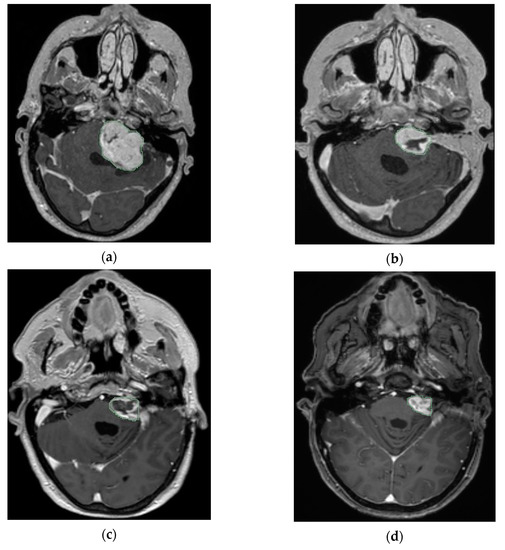

Over the past decades, surgery has been considered as the preferred treatment in patients harboring large VS [113,114]. In recent years, there is a trend towards the approach of planned SRS after planned subtotal resection (Figure 3).

Figure 3. An axial T1 MRIs with contrast for left VS (KOOS D), showing tumor shrinkage after the combined approach; A, is the image before surgery; B, after surgery and before GK; C, 6 months after GK; D, 5 years after GK (courtesy of Y. Temel).

The theory behind planned combined therapy is a safe resection minimizing the risk of FN injury and better control of the residual tumor by applying a dose of radiation [115,116,117]. Data related to the radiation type, dose delivered, recurrence, radiation-induced side effects and functional outcomes are summarized in Table 2.